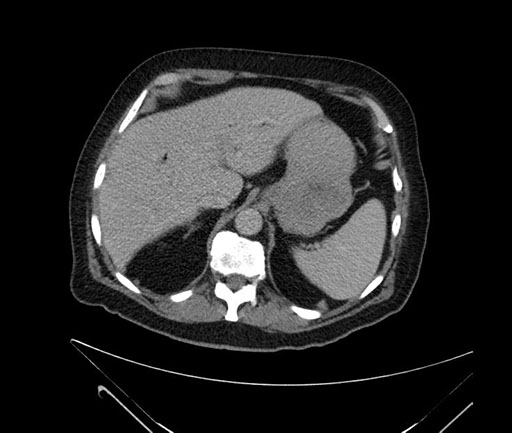

Whipple (pancreaticoduodenectomy) [case 7]

Axial - 3 months prior

Imaging analysis

Based on your CT findings, which issue(s) would give reason for "planned slowing down moment(s)" in this case?

Considering a standard Whipple procedure, what step(s) of the operation would you do differently in this case?